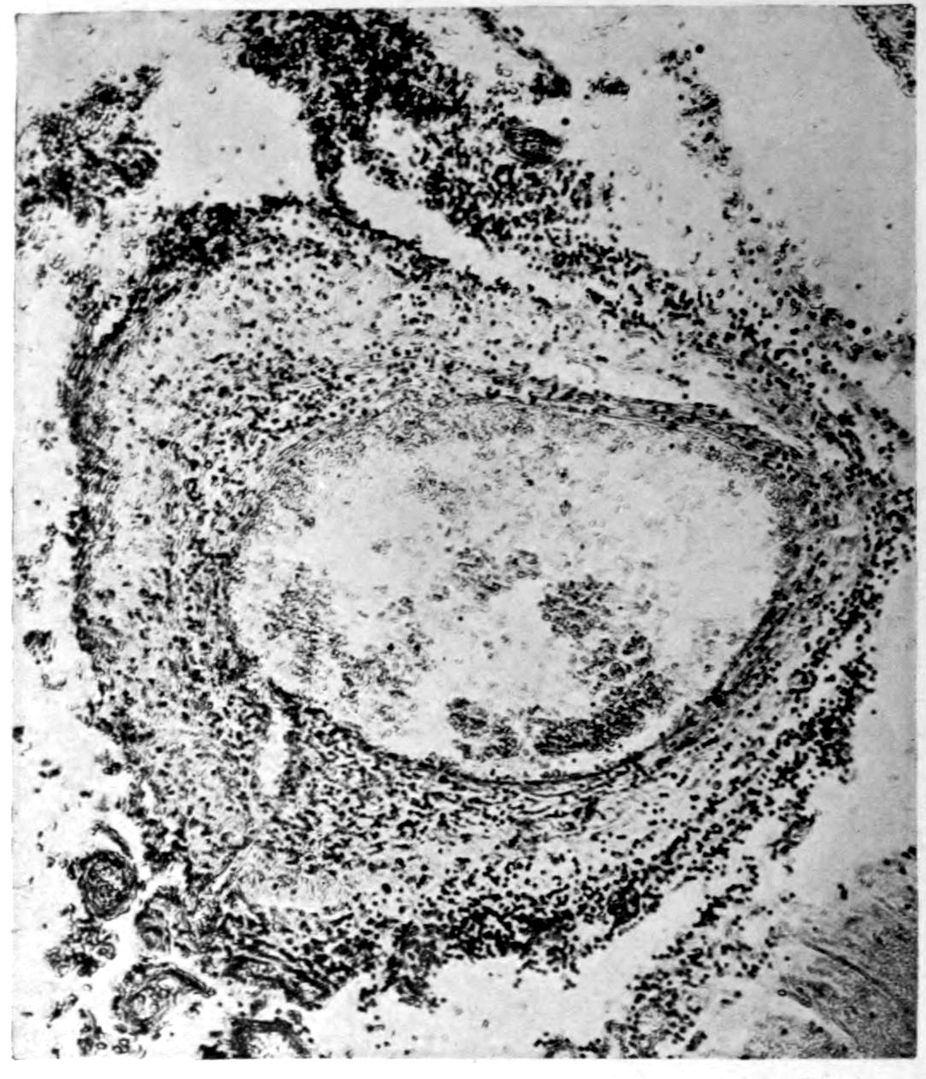

Apparent new formation of small blood vessel. Photographed by Dr. A. M. Barrett.

Rod cells (Stäbchenzellen) in paretic neurosyphilis. Photographed by Dr. A. M. Barrett.

Granular ependymitis—microscopic appearance of a marked example of “sanding” of ventricle.

41Characteristic and constant in paretic neurosyphilis is the Plasmocytosis and Lymphocytosis, Perivascular in distribution about small cortical vessels. There is also a characteristic (though characteristically less prominent) Plasmocytosis and Lymphocytosis, Meningeal in distribution. The pleocytosis of the spinal fluid, almost constant though variable in amount in life, is an indicator of the meningeal picture and less directly of the parenchymatous picture.

Granular Ependymitis (“sanding” of ventricle floors) is characteristic and may be regarded as part of the parenchymatous picture. This ependymitis is an indicator how chemical changes could be readily produced at least in the ventricular fluids, since the limiting membranes of the nerve tissue are here subject to multiple breaks. The “sanding” is a neuroglia reaction to these multiple small breaks (Weigert’s explanation).